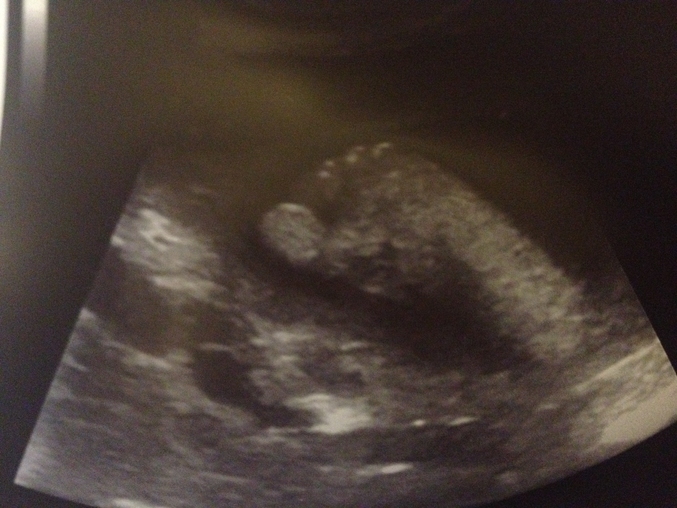

Идет 33 неделька!!!!!! Я так кайфую от беременности))))) животик вырос и он мне так нравится... Делали узи на 32 неделе, мы уже 1950 гр, 41 см, а стопа наша (на фото) 6,5 см!!! Так вот почему так больно по печени получается...))) Периодически бывает тонус, треники и бессонница! Последнее особенно часто... каждую ночь( А еще сегодня в 4:15